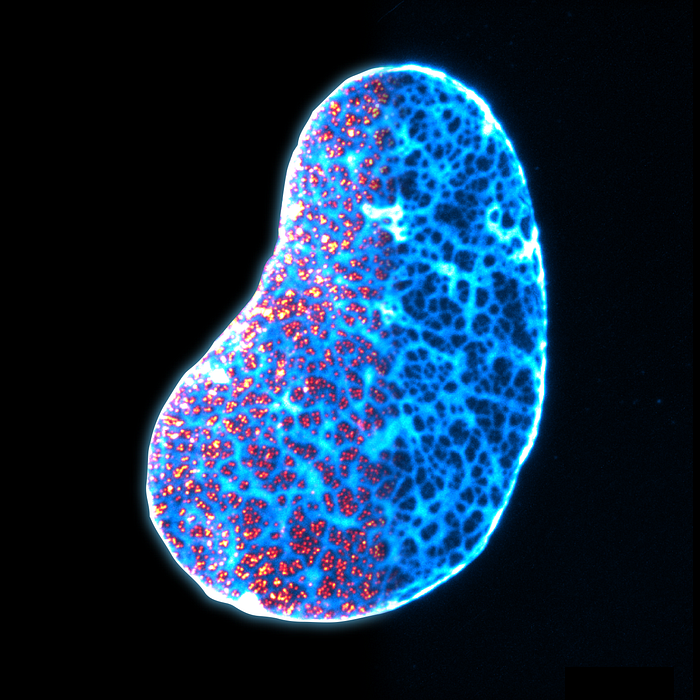

Imagine if we could use ultrasound to detect changes in tumor cells in real-time. While ultrasound imaging is a remarkable technology that has had a huge impact on medicine, it currently can’t see the specific functions of cells and molecules, only larger structures.

Imaging grantee Mikhail Shapiro is creating the first-of-it-kind contrast agent called acoustic biomolecules that will allow ultrasound to image the function of cells deep inside the body. A model of this technology enabled an ultrasound scan to detect a glioblastoma tumor inside a mouse brain (pictured here) — allowing researchers to see which cells are actively expressing genes. This new technology has the potential to change how we understand and treat health and disease — from neuroscience, immunology and cancer biology to development, gene therapy and cellular medicine.